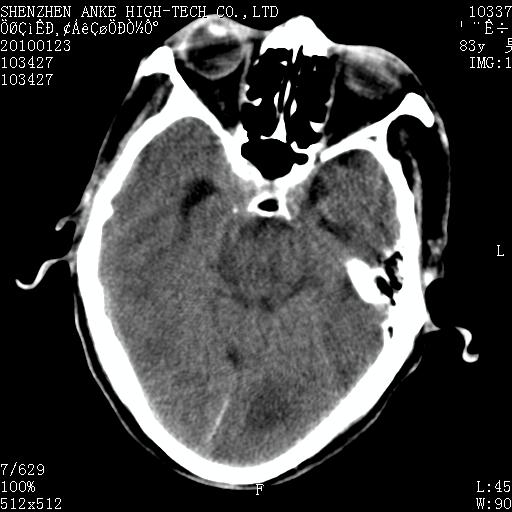

标题: CT24299:头颅平扫

患者:男,83岁,突发意思不清2天。原有脑梗塞病史。

肿瘤卒中,考虑恶性,依次淋巴瘤、转移瘤、恶性脑膜瘤、胶质母等,建议mri。

肿瘤卒中,考虑恶性脑膜瘤可能性大。

镰旁脑膜瘤卒中